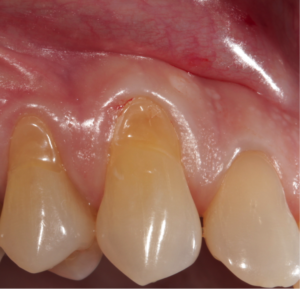

It is the condition where the cervical part of the teeth is affected. Cervical part is the region of tooth close to the gum line/gingiva. As we age, the forces that act on front/anterior surfaces of the teeth is far more damaging than the forces acting on the back/lingual surfaces of teeth. This type of age changes occur in front/anterior surface of the teeth. The anterior surfaces have comparatively less bone structure than lingual surfaces of the teeth. The thicker bone behind the teeth resists the forces and protects the tooth. Abrasion occurs due to improper tooth brushing technique, more force applied during brushing, clasps of the denture or due to abrasive contents in a toothpaste.

Abfraction

It is another such age change where a wedge shaped loss of tooth structure occurs near the cervical region of the teeth. In severe cases it can result in exposure of underlying layers of teeth and pulp exposure.